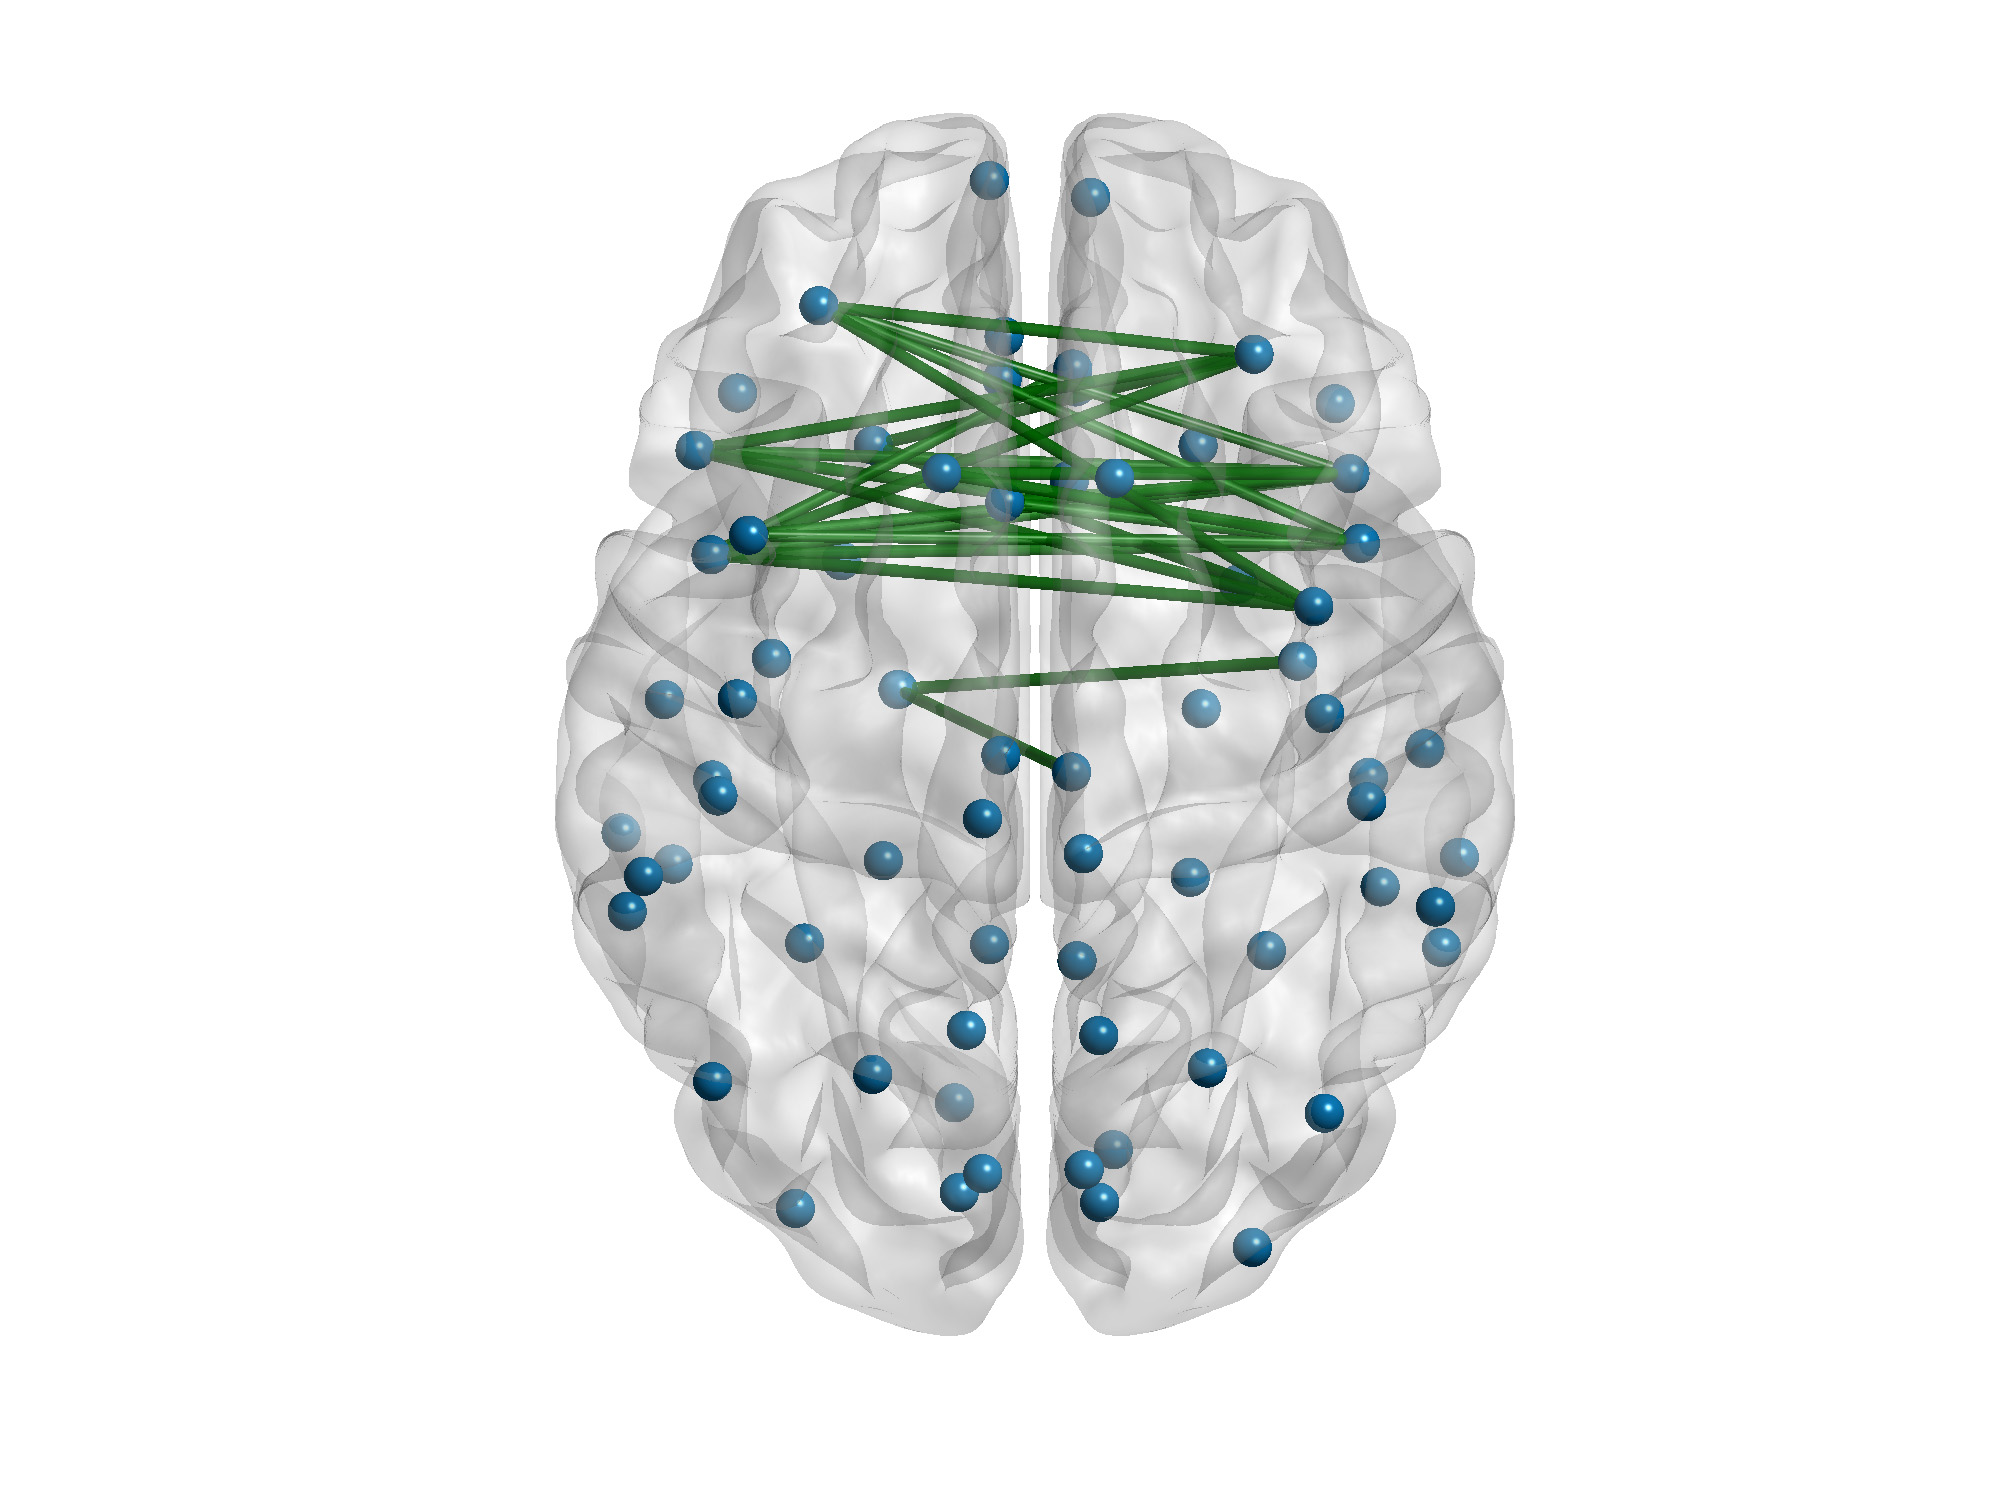

En verde, las conexiones de la creatividad. Imagen: Daniele Durante, University of Padova

Por último, los investigadores crearon algoritmos capaces de analizar estas informaciones, de identificar las diferencias entre las estructuras cerebrales de los jóvenes del experimento y de integrar en este informe los niveles de creatividad.

Analizando los datos, no encontraron diferencias estadísticas en la conectividad entre los hemisferios, ni entre hombres y mujeres. Pero cuando compararon a las personas que obtuvieron una puntuación de más de un 15 por ciento en las pruebas de creatividad con aquellas que estaban por debajo del 15 por ciento, descubrieron que las personas con mejor puntuación en creatividad alta mostraron más conexiones entre los hemisferios derecho e izquierdo. Las diferencias estaban principalmente en el lóbulo frontal del cerebro.

Según los investigadores, este estudio forma parte de la conectómica. Un conectoma es un mapa de las conexiones entre las neuronas del cerebro. La producción y el estudio de los conectomas se conoce como conectómica. En este caso, se refiere a la probabilidad de calcular la creatividad de una persona a través del análisis de la estructura de su cerebro.

Por último, los investigadores crearon algoritmos capaces de analizar estas informaciones, de identificar las diferencias entre las estructuras cerebrales de los jóvenes del experimento y de integrar en este informe los niveles de creatividad.

Analizando los datos, no encontraron diferencias estadísticas en la conectividad entre los hemisferios, ni entre hombres y mujeres. Pero cuando compararon a las personas que obtuvieron una puntuación de más de un 15 por ciento en las pruebas de creatividad con aquellas que estaban por debajo del 15 por ciento, descubrieron que las personas con mejor puntuación en creatividad alta mostraron más conexiones entre los hemisferios derecho e izquierdo. Las diferencias estaban principalmente en el lóbulo frontal del cerebro.

Según los investigadores, este estudio forma parte de la conectómica. Un conectoma es un mapa de las conexiones entre las neuronas del cerebro. La producción y el estudio de los conectomas se conoce como conectómica. En este caso, se refiere a la probabilidad de calcular la creatividad de una persona a través del análisis de la estructura de su cerebro.